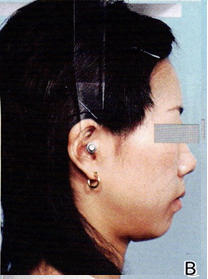

矯正前 矯正後

この様に顔貌が変化してしまいます。これはメリットでありデメリットでもあります。

主訴に顔貌の変化を希望するか?希望しないか?

良く確認する必要があります。

当院では顔貌を変化させる抜歯矯正は実施しておりません。